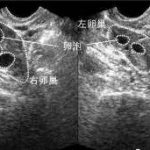

随着社会环境的改变,人们生育的能力在降低,而生育的要求却在提高,生育技术领域面临越来越严峻的考验。近年来随着科技的不断进步,试管婴儿已经不是那么困难的事情。所谓试管婴儿,是指采用人工方法让卵细胞和精子在体外受精,并进行早期胚胎发育,然后移植到母体子宫内发育而诞生的婴儿。